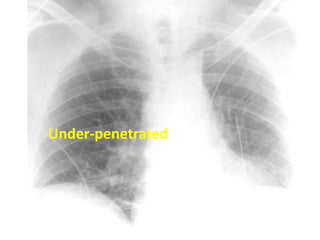

Exposure : You must barely see the thoracic vertebrae

behind the heart

Underpenetrated

Under-penetrated